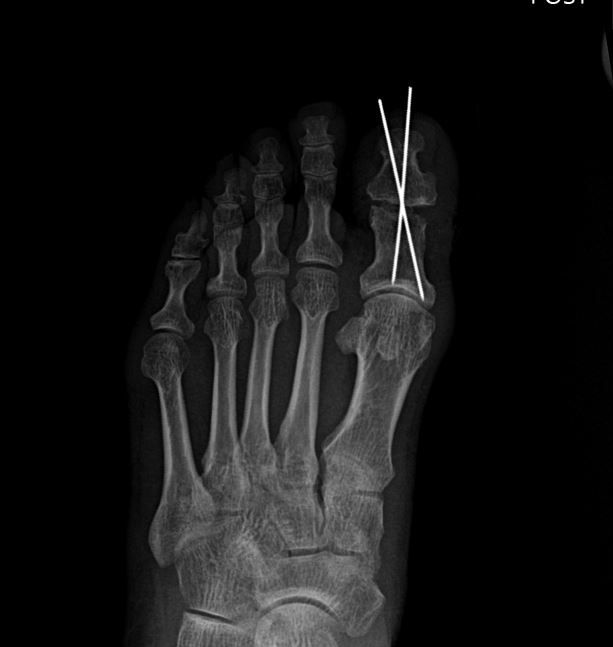

위와 같이 골절된 파편을 모아 금속 핀으로 고정하는 수술을 받으셨습니다. 사업장에 의무적으로 가입되어 있는 산재보험을 통해 보상받으실 수 있습니다. 고@@님은 다행히 보상파트너를 만나기 전

사진을 보셨다 싶이 잘 유합되어

아무 장해가 없는 듯 보였습니다.